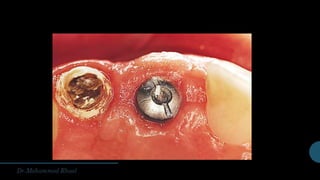

Components of dental implant

fixture

Abutment

Gingival former

Impression transfer

Analogue